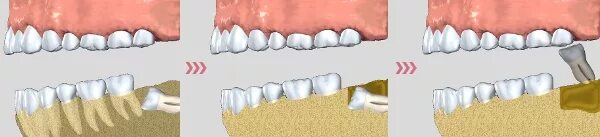

Удалить 7 зуб сверху